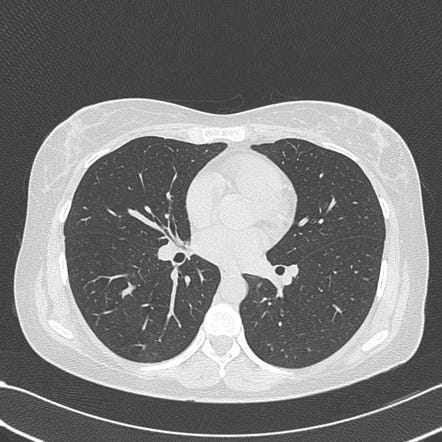

Idiopathic pulmonary fibrosis (IPF) is the most common form of interstitial lung diseases. It affects approx. 100,000–200,000 people in the U.S. and approx. 30,000 to 40,000 new cases are seen in the U.S. every year. The clinical presentation is often as an elderly man who presents with shortness of breath and low oxygen saturation in the blood (hypoxemia). Physical examination often reveals fine crackling sounds on lung auscultation, also known as ‘Velcro’ crackles. CT scan of the lungs is characterized by subpleural cysts, traction bronchiectasis and honey-combing appearance of the lung, especially in the peripheral regions. The treatment options are limited despite recent drugs like pirfenidone, and the life expectancy is often limited to less than 5 years after the diagnosis.

In this pilot experiment, our aim was to use a convulational neural network to classify CT scan images into IPF or normal. Since, this was a pilot experiment and this is not a very common disease, our image dataset consisted of fourteen CT scan images of IPF from different patients (with the characteristic features of IPF), and nine CT images of normal lung from different patients. CT scan images of IPF patients were annotated to highlight the abnormal areas with subpleural cysts, honey-combing, etc. Google Colab Python 3.6 environment with a Nvidia GPU and 64GB RAM was used.